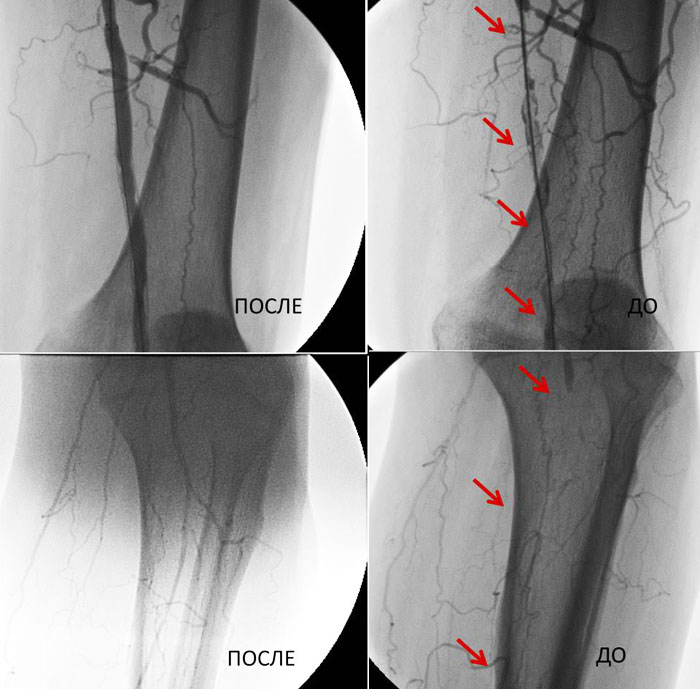

Arterial rekonstruksiyaların nəticələri

Xilas edilmiş aşağı ətraflar